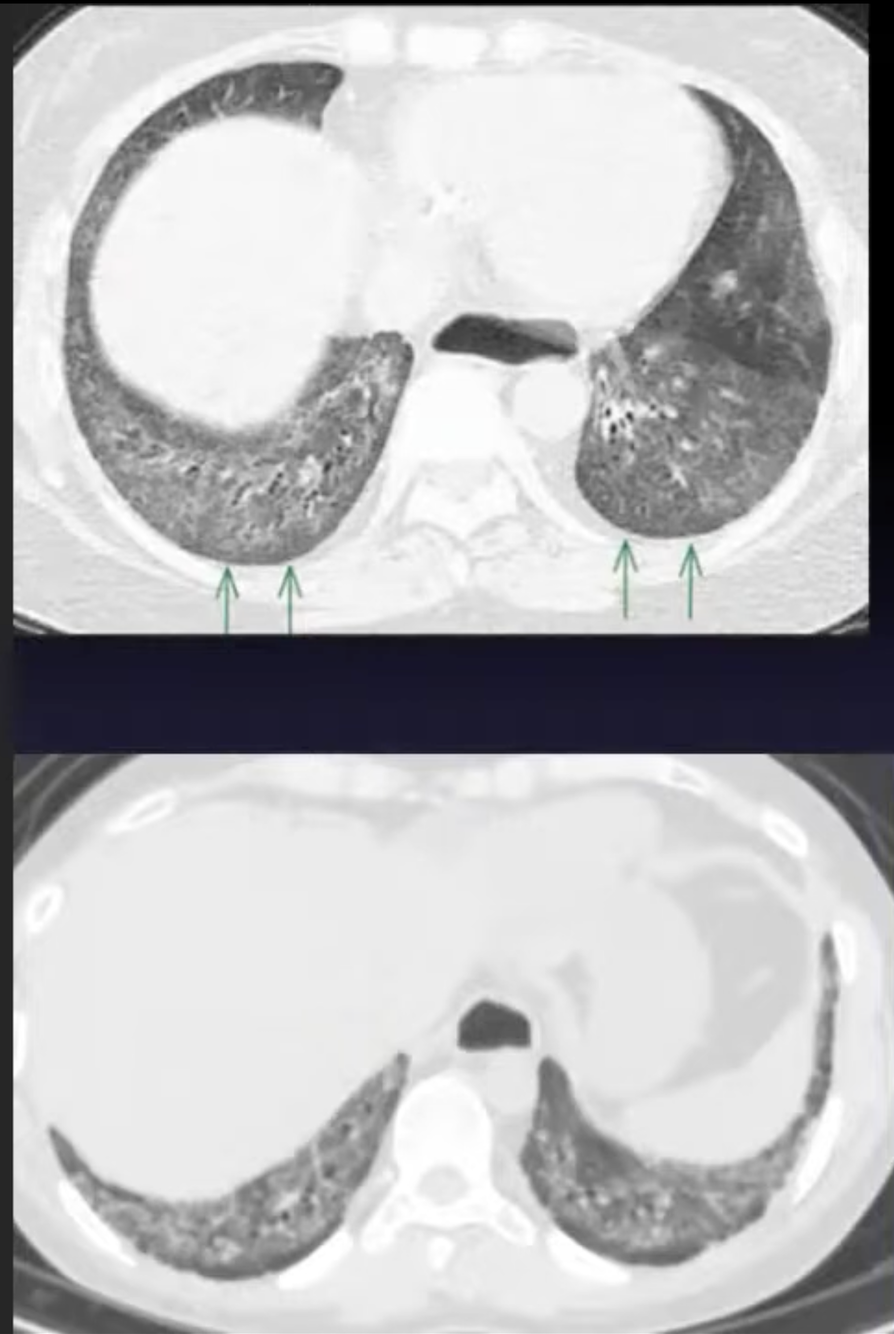

Perfectly

3

Q

Preservação subpleural + dilatação esofágica

A

Fibrose com reticulado e preservação subpleural

Esclerodermia

PINE fibrótica

How well did you know this?

Reticulacao + bronquio dilatado

PINE